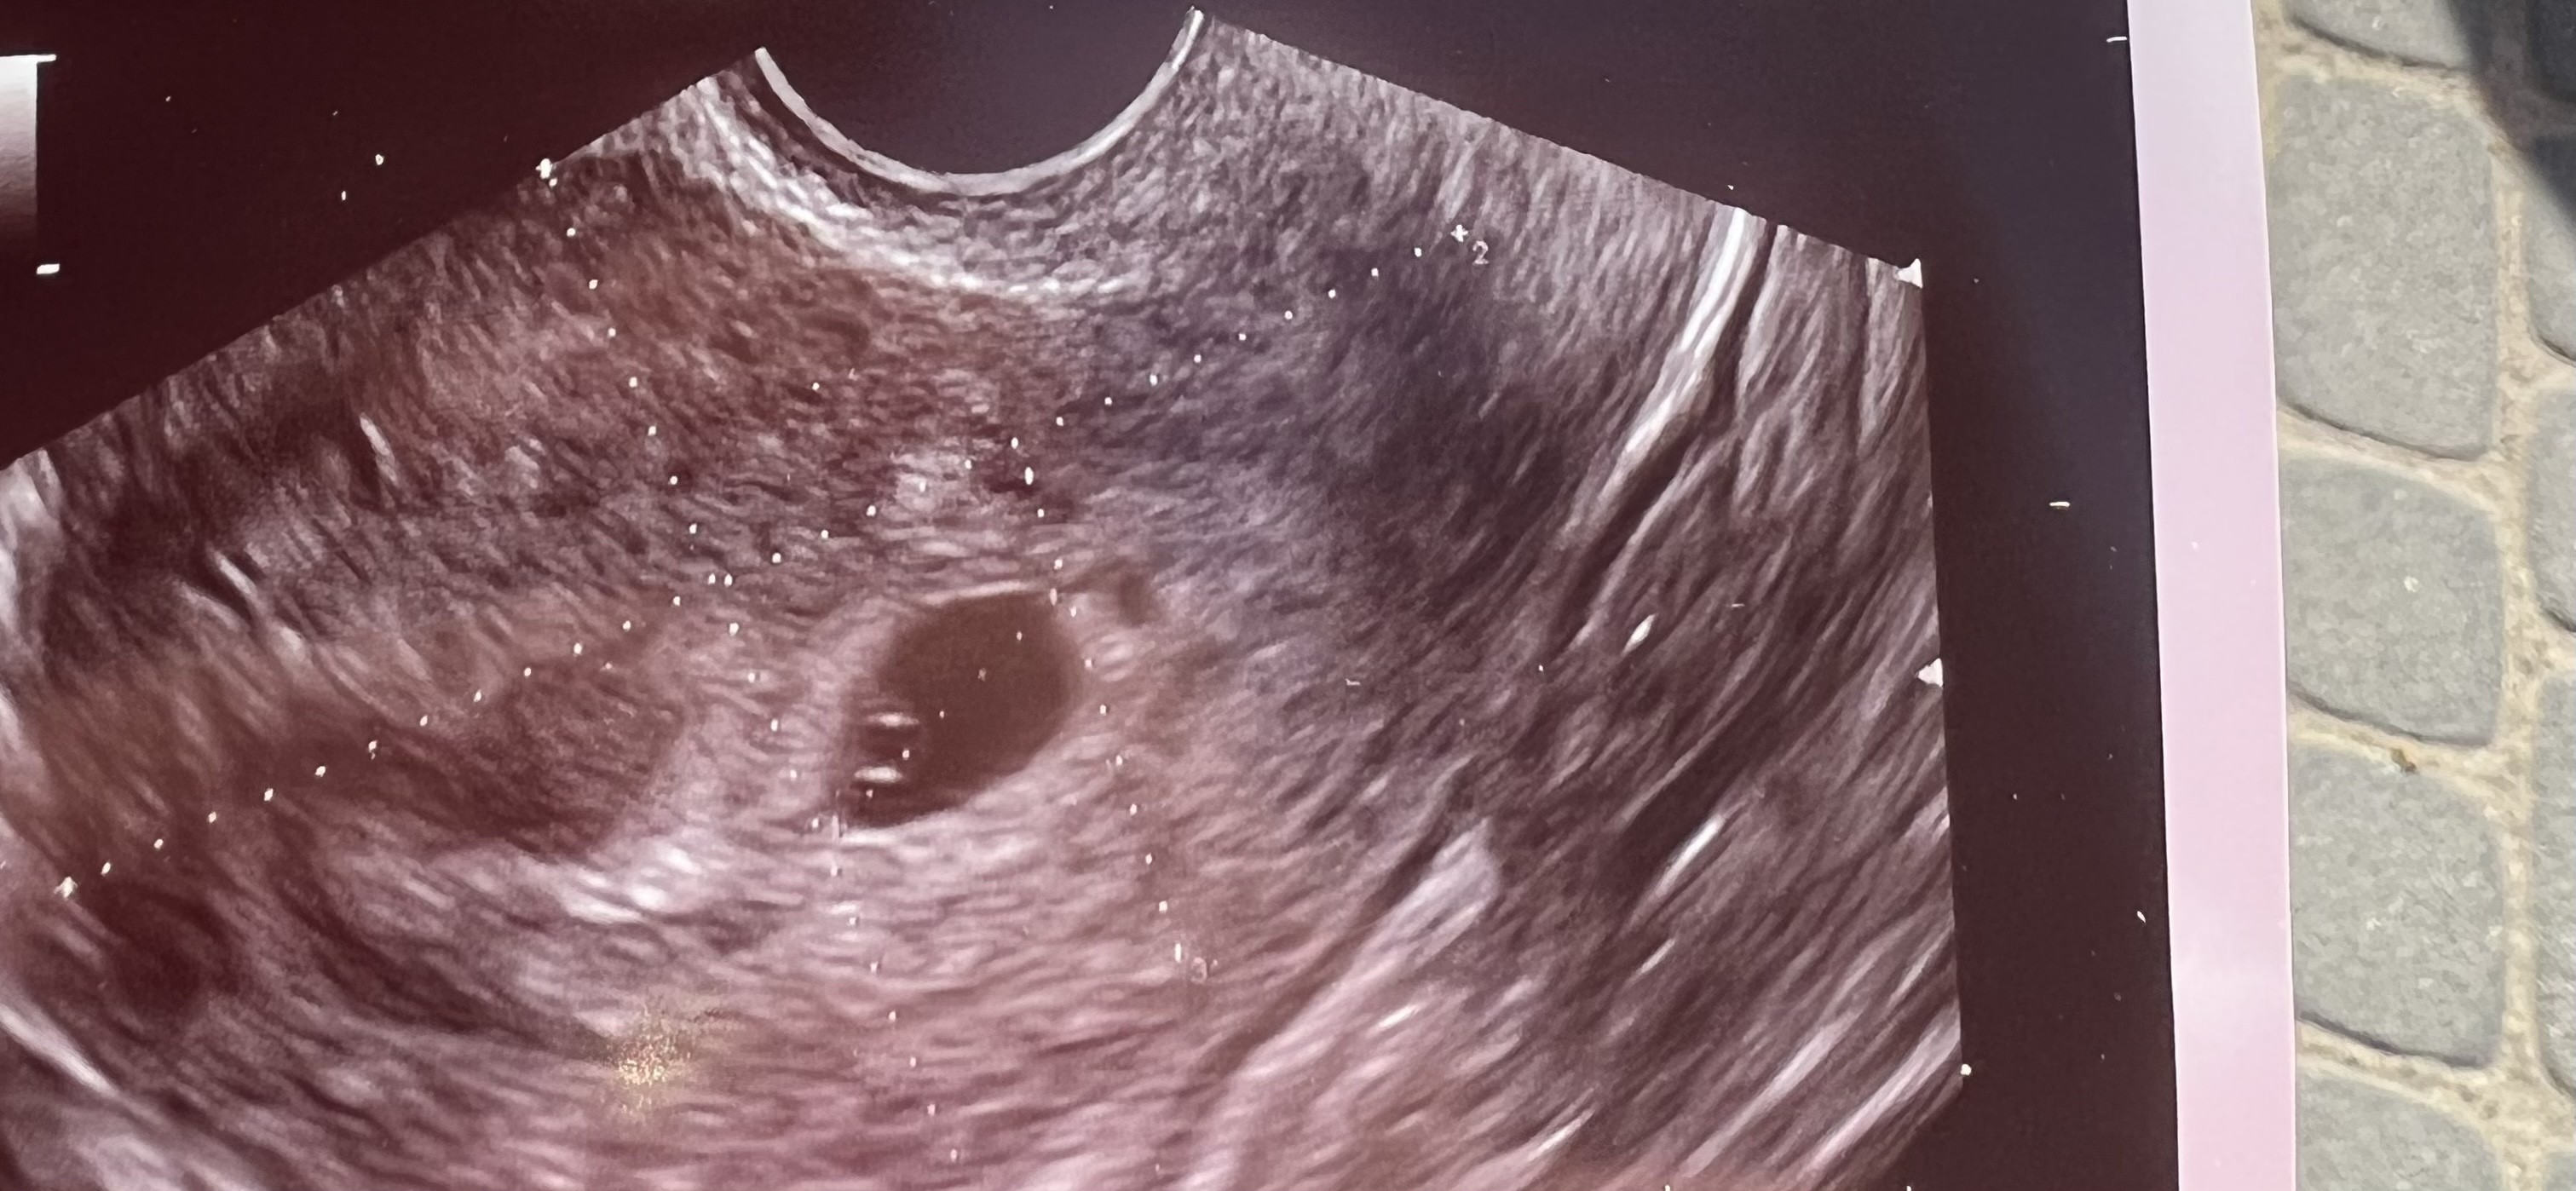

Zobacz załącznik 1403993

U mnie dziś pokazało się tak po 6 latach starania ... Jestem w jeszcze większym szoku i teraz ogromnie się boje ze to jednak jakas choroba ....Cześć, któraś styczniowa mama już wie? Mi kalkulator pokazuje termin na 02.01 lub po małej korekcie długości cyklu 06.01.

Żadna chorobaU mnie dziś pokazało się tak po 6 latach starania ... Jestem w jeszcze większym szoku i teraz ogromnie się boje ze to jednak jakas choroba ....

Już chyba sama sobie wkręcam , przez tyle lat nic a tu nagle brak okresu i dwie grube krechy , oczywiście odczytałam się w internecie i tych chorobach i testach pozytywnych że teraz wariuje.Żadna choroba!